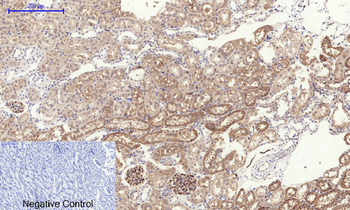

Immunohistochemical analysis of paraffin embedded Human astroglioma tissue labeling Tau with orb1294394 at 1/300.

Immunohistochemical analysis of paraffin embedded Human brain tissue labeling Tau with orb1294394 at 1/200.

Immunohistochemical analysis of paraffin embedded mouse Alzheimer’s tissue labeling Tau with orb1294394 at 1/1000 RT 1hr. Epitope Retrieval methods: Citrate Buffer, pH 6.0.